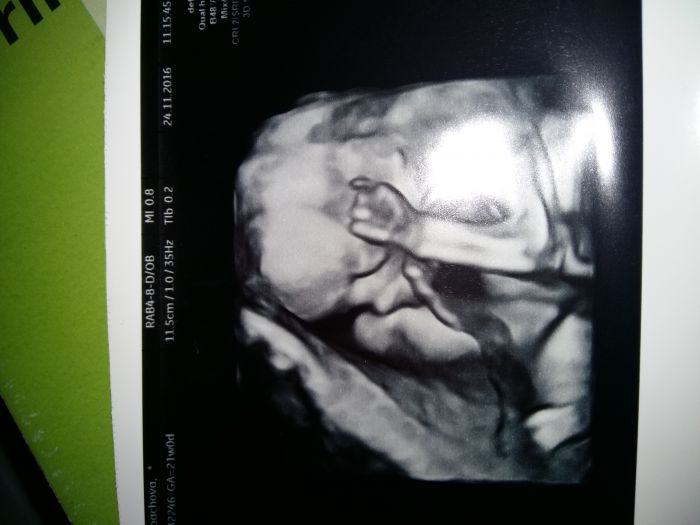

, ale sleduji vas bedlivě... Přeji všem hlavně zdravíčko a zdravá miminka... Zkusím dát fotecku malýho Lukáška

[957596] Jee to jsou krásný fotečky :)) Mně na screeningu 3D nedělala, ani mi to nenabídla. Tak jsem se na to včera ptala v poradně, a jsem objednaná na 23.12., tak snad nám Adámek ukáže před Vánoci tvářičku a budeme mít hezkej dáreček. Včera v poradně jsem se musela smát...při UTZ byl malej krásně otočenej k nám, bylo vidět jak otvírá pusinku a jakoby mlaskal. Měla jsem zrovna v puse bonbon, třeba to cítil